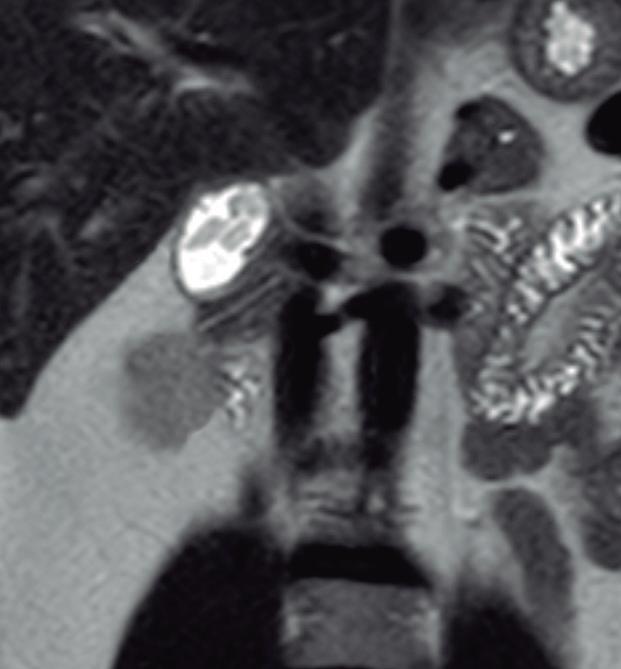

Páncreas Anular

Consiste en una anomalía de la migración del brote pancreático ventral, el cual no rota o lo hace de manera incompleta, resultando en la presencia de tejido glandular pancreático a la derecha del duodeno, rodeando a su 2° porción (Figura 8). Han sido descriptos dos subtipos: el extramural, donde el conducto de Wirsung rodea al duodeno uniéndose al conducto pancreático principal; y el intramural, donde el tejido pancreático se entremezcla con la pared duodenal y sus secreciones drenan directamente a la luz a través de conductos muy pequeños.16

En las imágenes encontramos parénquima pancreático rodeando a la 2° porción duodenal, habitualmente en toda su circunferencia y en ocasiones de manera incompleta. En la colangio-RM es posible visualizar al conducto pancreático a la derecha del duodeno, con un recorrido que se dirige a la ubicación de la papila mayor (Figura 9).17

9. Páncreas anular

8. Esquema del páncreas anular

A) Resonancia magnética secuencia T1 con gadolinio, plano axial. Las flechas señalan el parénquima del páncreas prolongado hacia la derecha “abrazando” a la 2° porción duodenal (cabeza de flecha). B) Resonancia magnética, secuencia T1 con gadolinio, plano axial, corte más caudal al previo. Las flechas nos muestran al páncreas rodeando de manera completa a la 2° porción del duodeno. C) Resonancia magnética, secuencia T2, plano coronal. La flecha señala presencia de parénquima glandular y conducto pancreático a la derecha del duodeno (cabezas de flecha). D) Resonancia magnética, secuencia T2, plano coronal, corte posterior al previo. El páncreas anular y su conducto de drenaje rodean en forma completa al duodeno (cabezas de flecha). E) Colangio-RM. El conducto del páncreas ventral (flechas) hace un giro, rodea al duodeno (cabeza de flecha) y se une al conducto pancreático principal para drenar en la papila mayor. F) Colangio-RM. La imagen magnificada muestra con mayor detalle el recorrido del conducto de Wirsung en el contexto de un páncreas anular.